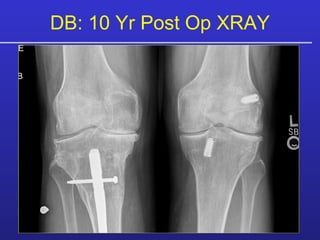

Patient Example DB 47 YO Male Skier R Knee:  Chronic Pain Moderate to Severe Bilateral Pain

DB: Right Knee Right Knee:  09/91:  Medial Meniscectomy, Drilling MFC, Chondroplasty 12/97: (triple) Medial Meniscus Allograft, Osteotomy, Art Cart MFC, MFx LFC 05/98: Revision Osteotomy, Medial Meniscectomy, Debridement, MFx MTP 10/2000: Ilizarov, Meniscectomy, Chondroplasty Pre-Op XRAY

DB: 10 Yr Post Op XRAY

DB: 10 Yr PostOp 63 YO, Tegner = 6, Skis 30+ days/yr, Snow skis 50+ days/yr.